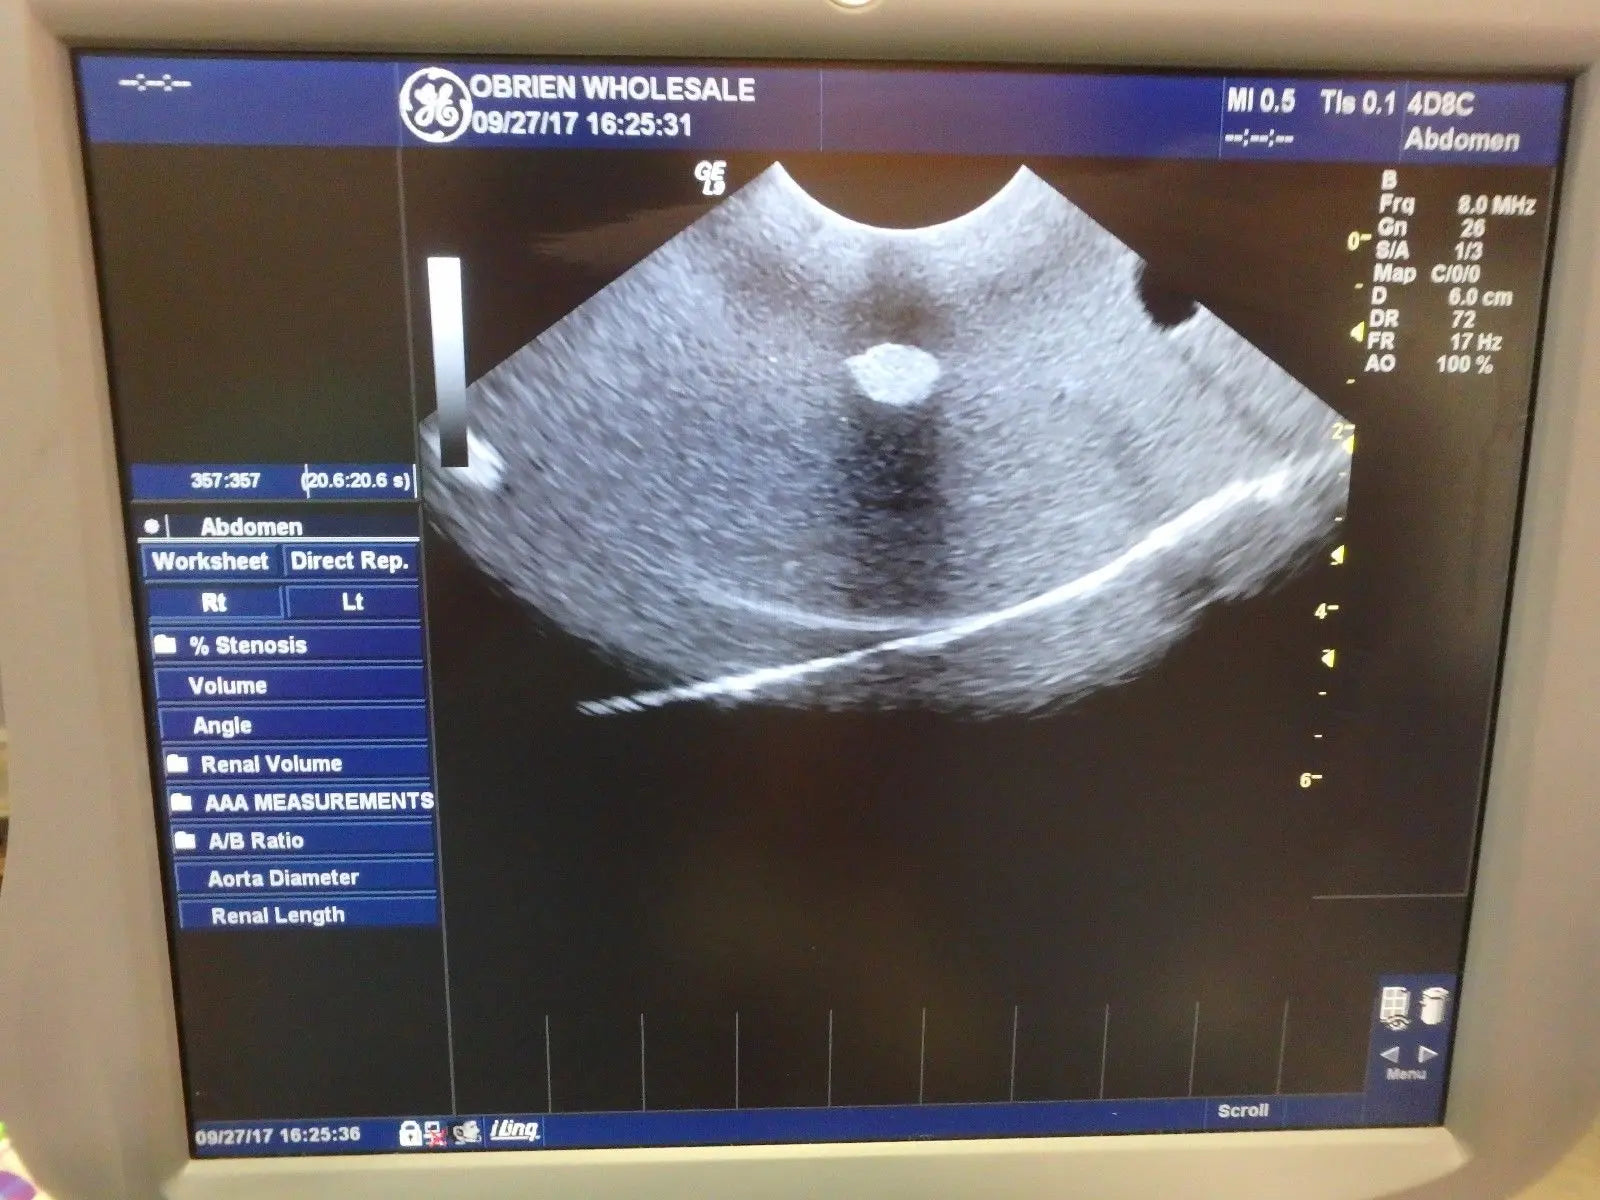

Seller Notes:âFully functional. Tested using a GE Logiq 9 with a breast phantom. Shows signs of use. Includes everything shown.â

Model: GE 4D8C 3D/4D Curved Array 3.5-9MHz Ultrasound Tra

The GE 4D8C ultrasound transducer probe operates within a frequency range of 3.5-9MHz, making it ideal for high-resolution imaging. This device harnesses advanced 4D capabilities, allowing healthcare professionals to visualize complex anatomical structures in real-time. Consequently, it enhances diagnostic accuracy and aids in better patient care. Users can expect clear and detailed images, which significantly improve evaluation and treatment processes.

This ultrasound transducer is versatile and adapts to various clinical applications, including obstetrics, cardiology, and vascular imaging. Medical practitioners can utilize the instrument for routine examinations and specialized diagnostics. Another advantage is its curved array design, which provides an extended field of view, allowing for easier and quicker assessment of the patient's condition. Hence, it streamlines workflows in busy clinical environments.